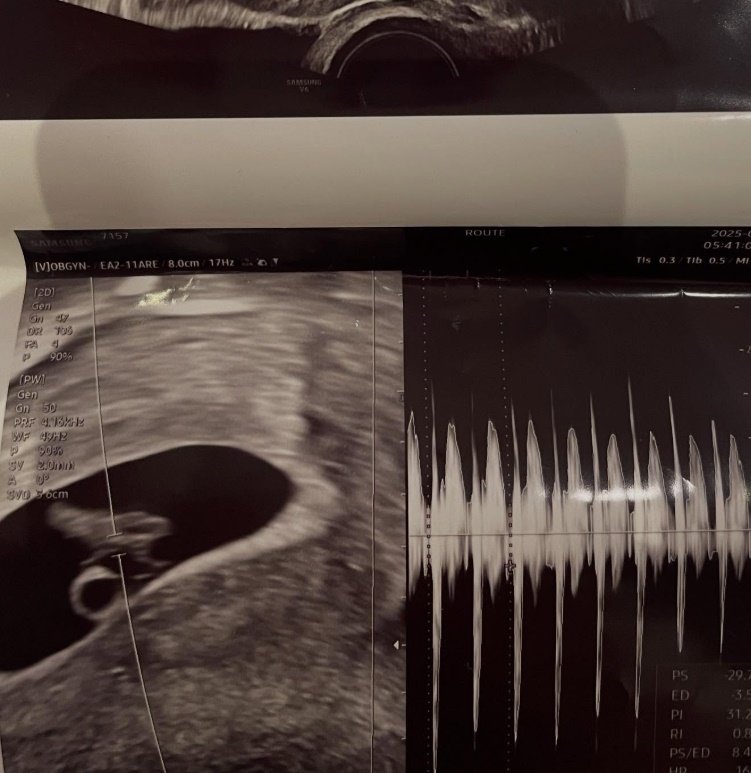

‘하트시그널3’에 출연했던 서민재(서은우)가 임신을 발표했다.

서민재는 2일 오후 자신의 SNS에 “아빠 된 거 축하해 OOO”이라는 글과 함께 사진을 여러 장 공개했다.

공개된 사진에는 서민재가 임신한 것을 추측할 수 있는 초음파 사진과 더불어 남자친구로 예상되는 인물의 모습이 담겨있다.